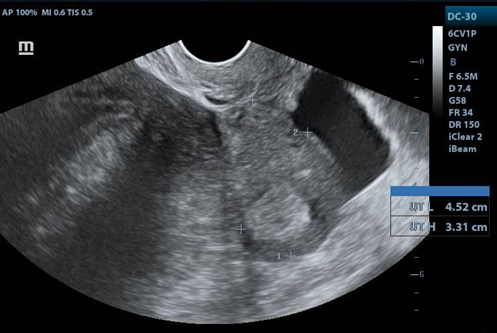

Transvaginal USG: uterus in AVF 4.5x5x3.3cm, LE 12.3mm. Right ovary: 4.8x3.6x3.7 cm vol. 34cc, with a tumor measuring 11.2x8.6cm, solid, with homogeneous and hypoechoic echotexture, with posterior acoustic shadow and Doppler flow uptake. Left ovary: 5x5x2.2cm vol. 19.6cc.

USG Transvaginal

1. Image of the uterus in longitudinal view. With free fluid in the cul de sac.

1. Right adnexa, with heterogeneous image, hypoechoic mass, with clear border. with distance of 11.26X11X8.6cms.

1. Acoustic attenuation posterior a hypecoic mass en right adnexa.